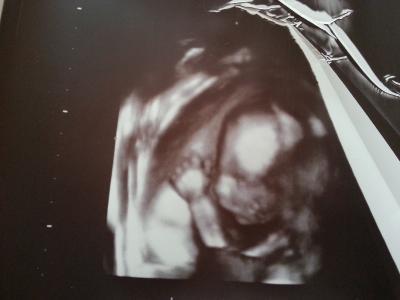

Ultraschall war so toll bin so verliebt sie hat mal in 3d gemacht man der kleine Mann ist so süß. Und meine Plazenta ist auch wieder da wo sie sein soll

Bild zu wieder da und so verliebt - Forum für November - Mamis